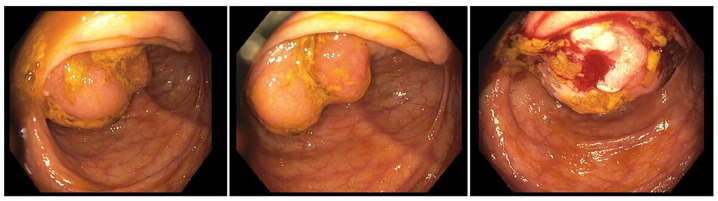

子宫内膜异位症是一种妇科疾病,可出现在盆腔和盆腔外部位,包括胃肠道。盲肠和阑尾受累是罕见的,可以表现为贫血,模仿恶性肿瘤。本病例为一50岁女性,表现为症状性贫血。影像显示盲肠及阑尾肿块伴淋巴结病变,可能为恶性肿瘤。结肠镜检查显示可疑肿瘤,但活检结果不确定。手术切除发现广泛的子宫内膜异位症累及盲肠和阑尾。病理证实酷似子宫内膜异位症。术后,患者的贫血得到改善。本病例强调胃肠道子宫内膜异位症通常无症状且难以诊断。其结肠肿块的表现强调了广泛区分的必要性。当怀疑有恶性肿瘤时,手术干预至关重要。

Endometriosis is a gynecological condition that can manifest in pelvic and extra-pelvic sites, including the gastrointestinal tract. Cecal and appendiceal involvement is rare and can present as anemia, mimicking malignancy. The discussed case is of a 50-year-old female who presented with symptomatic anemia. Imaging revealed a cecal and appendiceal mass with lymphadenopathy, raising concern for malignancy. Colonoscopy showed a suspicious tumor, but biopsy was inconclusive. Surgical resection revealed extensive endometriosis involving the cecum and appendix. Pathology confirmed endometriosis mimicking neoplasia. Postoperatively, the patient's anemia improved. This case highlights that gastrointestinal endometriosis is often asymptomatic and difficult to diagnose. Its presentation as a colonic mass underscores the need for broad differentials. Surgical intervention is crucial when malignancy is suspected.